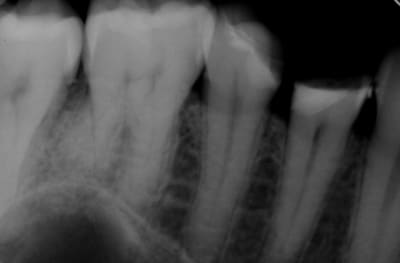

Alors comment traiteriez vous cette 24 asymptotique, qui présente un enorme délabrement sous gingival , notez que l'émail n'est plus soutenu par la dentine à aucun endroit ?

> Alors comment traiteriez vous cette 24 asymptotique, qui présente un enorme

> délabrement sous gingival , notez que l'émail n'est plus soutenu par la dentine

> à aucun endroit ?

1ère séance remontées de la marche distale au compo flow + compo de restauration / réalisation d'un IDS , le tout sous digue bien sur (voir radio jointe , désolé à l'envers))